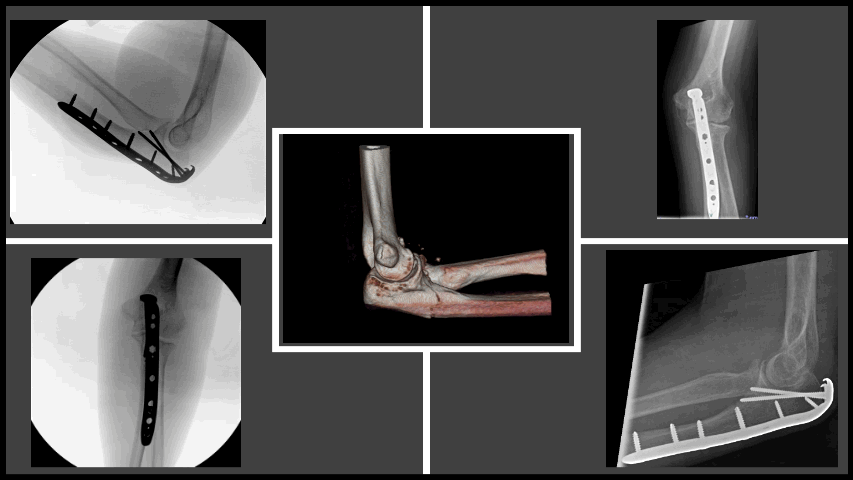

![]() Distal radius fracture | ![]() Bilateral total hip replacements | ![]() Fluoroscopy of clavicle fixation | ![]() Intra-articular distal humerus fracture |